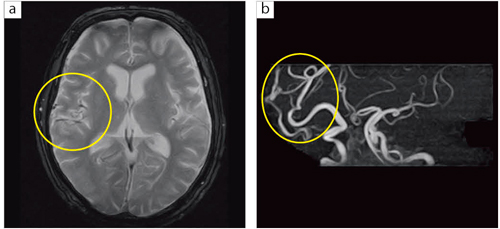

■症例4:脳動静脈奇形

74歳,男性。物忘れを訴えて来院。T2*強調画像(a)にて右シルビウス裂に異常な血管を認め,MRA(b)にて皮質静脈の拡張を認める。脳動静脈奇形と診断された。 a:T2*WI,FOV:220mm,TR/TE:1000/45,FA:30°,スライス厚:7.0mm b:MRA,3D TOF(MIP),FOV:160mm,TR/TE:37/6.5,FA:30°,スライス厚:1.2mm